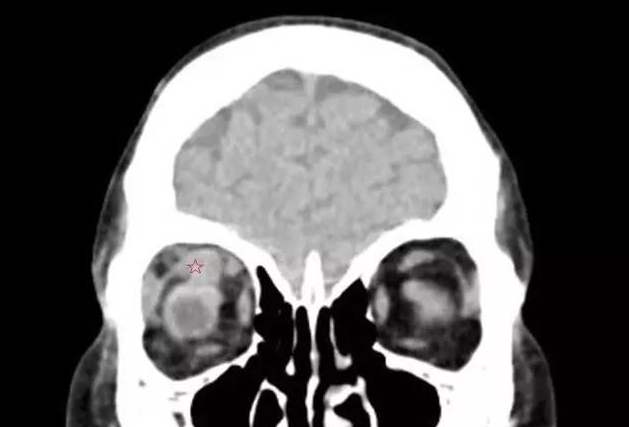

【导读】甲状腺相关眼病,是眼科较常见的疾病之一 。其包括:眼球突出、复视等,对患者的生活和工作带来极大的不便

甲状腺相关眼病,是眼科较常见的疾病之一 。其包括:眼球突出、复视等,对患者的生活和工作带来极大的不便。

谢仁艺副主任医师介绍,刘先生眼睛病变是因甲亢引起,导致双眼眼外肌发炎、肿胀、变性、纤维化, 终失去弹性,这也是他眼球转动不灵活引起斜视、复视的主要原因。